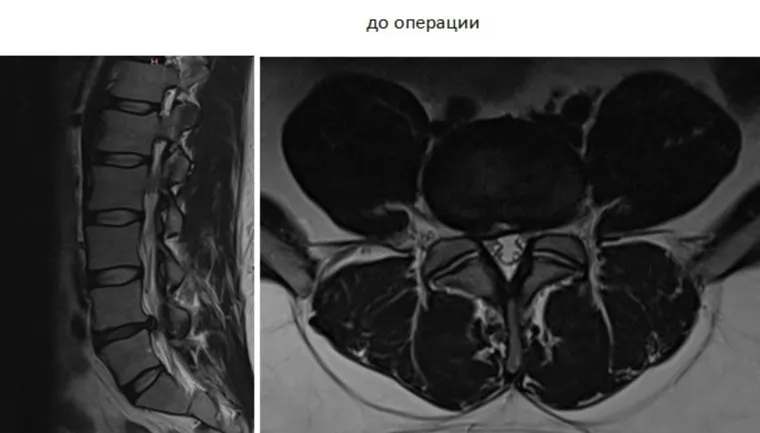

Врачи-нейрохирурги Центра имени Илизарова провели уникальную операцию по установке протеза поясничного диска 32-летнему жителю из Москвы. Благодаря титановому импланту пациент не будет испытывать болей, когда ходит, лежит, стоит или наклоняется. Об этом сообщает пресс-служба медучреждения.

Житель Москвы обратился в Центр им. Илизарова с болями в позвоночнике